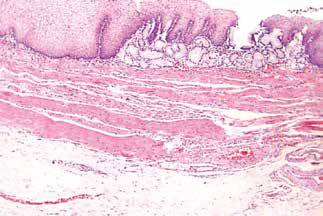

固有肌层

通常认为,食管上1/4至上1/3段的固有肌层由横纹肌组成,然而,只有很短(约5%)的近端食管固有肌层完全由横纹肌组成。随后的食管固有肌层由平滑肌和横纹肌混合组成,以平滑肌为主,稍多于50%的远端固有肌层全部由平滑肌组成。

近端食管。固有肌层由平滑肌束和横纹肌束混合而成。

虽然存在两种不同类型的肌肉,但它们可作为一个整体发挥功能。两种肌纤维层之间可见Auerbach神经丛和其相关的Cajal间质细胞,间质细胞也可见于固有肌层内。